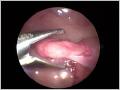

Eierstock mit Fassinstrument

Das Ovar ist identifiziert und wird mit einem Instrument gefasst.